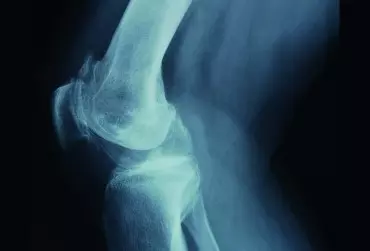

Palpacja stawu kolanowego

Wartościowym uzupełnieniem wiedzy na temat budowy ludzkiego ciała jest umiejętność badania go za pośrednictwem dotyku.